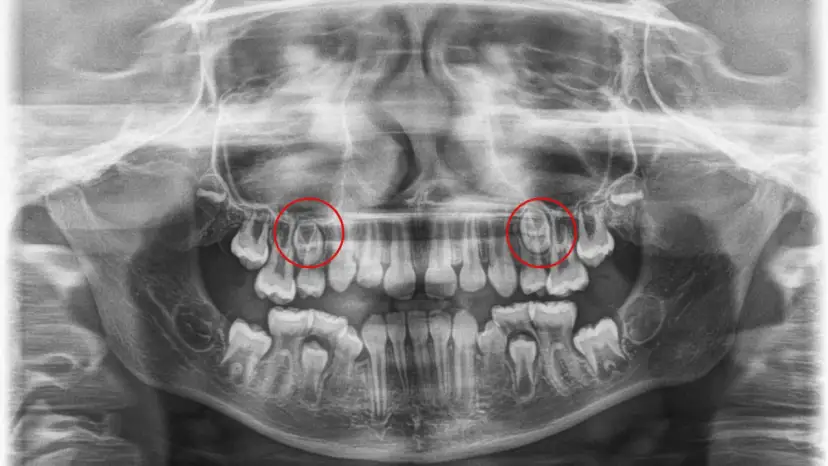

Brak zawiązków zębów stałych u dziecka? Dowiedz się, co robić, aby pomóc swojemu dziecku w tej trudnej sytuacji i jakie są dostępne opcje leczenia.